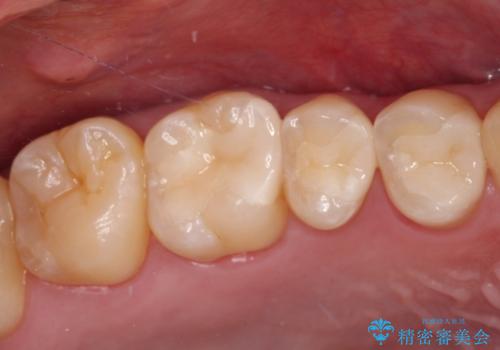

詰め物が外れた セラミックインレー修復

- 以前治療した詰め物が外れてしまい、冷たいものがしみることを主訴として来院された患者様です。

むし歯がないことを確認し、セラミックインレーにて修復するととしました。

適合の良いセラミックインレーの装着により、冷たいものがしみる症状はなくなりました。